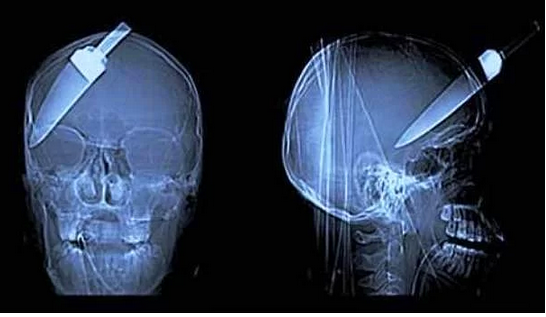

Kafaya saplanan bıçak

Silahlı soygun kurbanı bu arkadaş, tamamen iyileşmiş